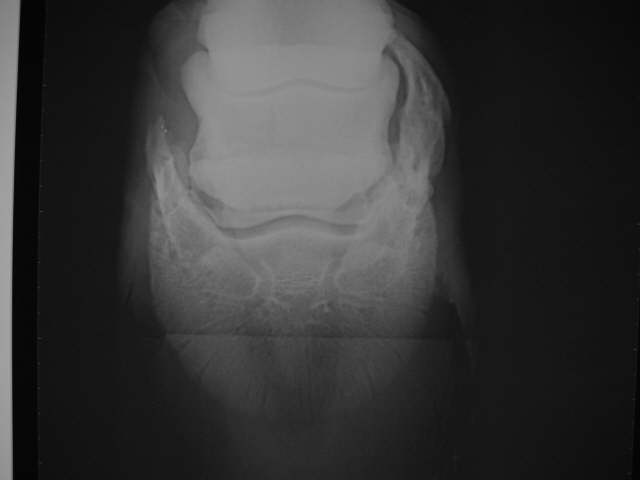

Hufknorpelverkn.

Rechts massive Hufknorpelverknöcherung